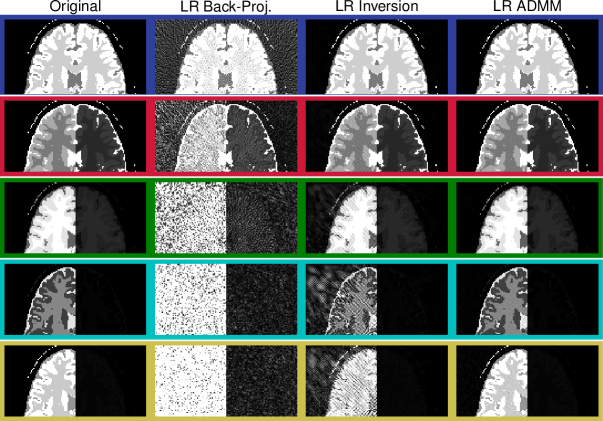

When using 32 spokes per TR, all reconstruction techniques converge to very similar results (Fig.ย 11). This is also reflected by the comparably constant relaxation times measured within a region of interest in the frontal white matter (Tab.ย 1). Note that B0subscript๐ต0B_{0} drifted significantly during the time needed to obtain all 323232 spokes. Consequently, the relaxation times are biased and deviate from those obtained when reconstructed from the first repetition only (Fig.ย 10). This effect originates from the sensitivity of balanced SSFP sequences to B0subscript๐ต0B_{0} variations and a detailed study of these effects is beyond the scope of this paper.

Figure 11

The depicted parameter maps with a matrix size of 192ร—192192192192\times 192 were reconstructed from 32ร—8413284132\times 841 radial spokes, which were acquired in vivo within 7.357.357.35ย minutes. Coil sensitivity profiles of a 16 channel head coil (compressed to 8 virtual coil elements) were incorporated. Note that the relaxation times are biased by B0subscript๐ต0B_{0}-drifts during the scan, by slice profile imperfections and by magnetization transfer effects.

Refer to caption